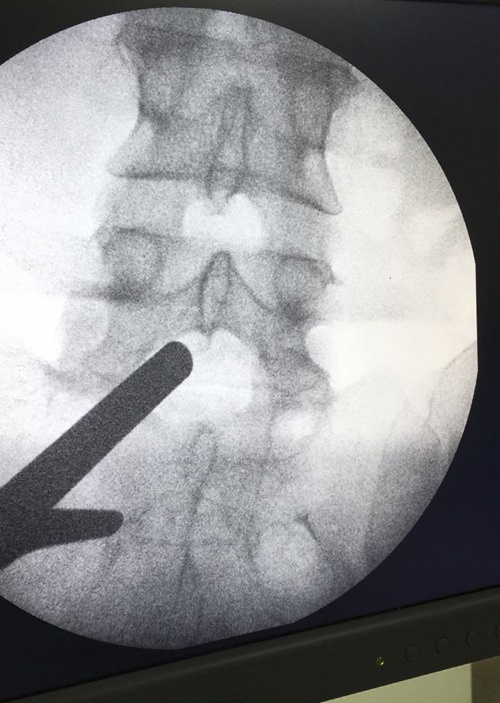

A equipe do centro cirúrgico do Hospital da Região Leste (HRL), no Paranoá, realizou, nesta quinta-feira (16), a primeira cirurgia endoscópica de coluna vertebral da rede pública de saúde do DF. A técnica, trazida da Coreia do Sul, utiliza monitores de alta resolução para visualizar o local exato onde deverá ser feito o procedimento. No caso da paciente, era uma cirurgia de urgência para retirar uma hérnia de disco. Ela se recupera bem e já terá alta nesta semana.

“Pela abertura da incisão, usamos um sistema de dilatadores para colocar uma cânula [tubo] de trabalho”, explica. “Através dela é colocado o aparelho de endoscopia, específico para conectar a câmera e a fonte de luz. Com isso, foi possível tirar o fragmento de disco que causava a dor lombar na paciente e afetava seu quadro físico.”